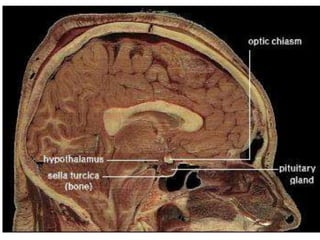

• The hypothalamus is located below the thalamus,

• Forms the ventral part of the diencephalon.

– Anterior- optic chiasm,

– laterally - sulci formed with the temporal lobes,

– posteriorly by the mammillary bodies

• The smooth, rounded base of the hypothalamus is the tuber

cinereum

• The pituitary stalk descends from the median eminence.